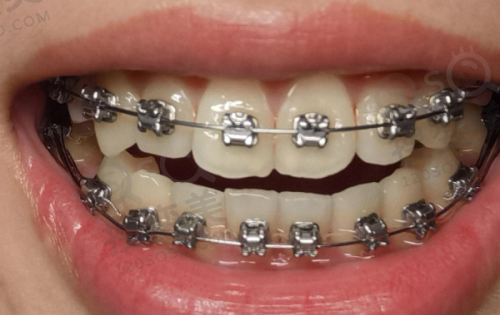

陶瓷半隐形矫正则结合了金属矫正和隐形矫正的优点。它的矫正器颜色接近牙齿颜色,相对美观,同时矫正成效也非常显著。这种矫正方式适合那些对美观有一定要求,但又希望矫正成效好的患者。

实例二:患者[姓名2],是一位成年人,由于牙齿咬合不正,导致咀嚼功能受到影响。[牙医姓名3]为他采用了陶瓷半隐形矫正技术。在矫正过程中,患者没有感到明显的不适,而且矫正成效非常理想。现在,患者的牙齿咬合正常,咀嚼功能也得到了改善。